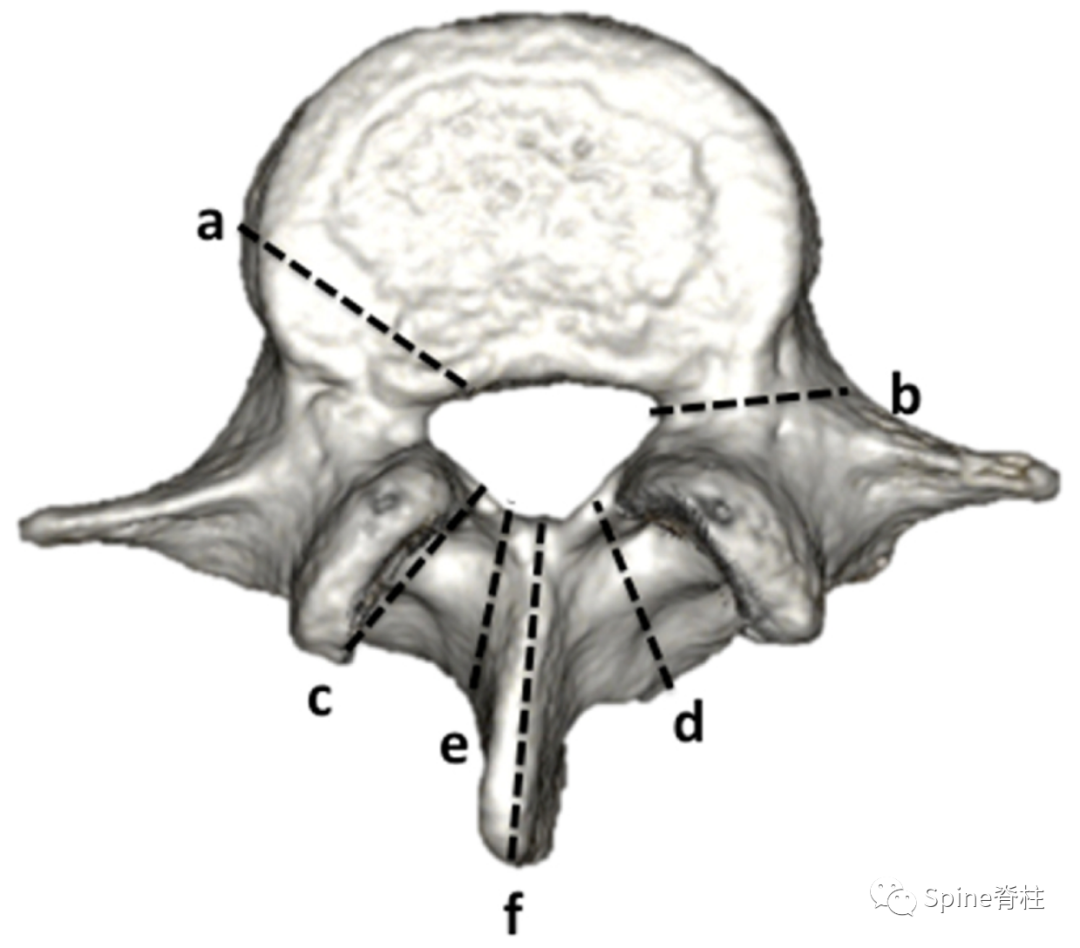

目前,学者们对腰椎峡部关注的较多,且研究的也比较深入。McCullochTransfeldt提出了“侧方支撑” (lateral buttress) 的概念,认为腰椎峡部对介于其间的结构提供重要的结构性支撑,将腰椎峡部定义为连接下关节突的外上缘与横突/椎弓根的骨性桥梁。

在脊柱解剖和建筑结构上,侧方支撑用于在两个垂直结构之间分配荷载,降低其连接处的失效风险。PMID: 12221372

也有学者将侧方支撑称之为“侧方峡部” (lateral pars/pars lateralis),传统峡部称为关节间部峡部 (pars interarticularis)

关节突间峡部与侧方峡部

2002年,一项解剖学研究测量了人尸体标本腰椎侧方支撑的表面积,结果发现侧方支撑面积最大的节段是L1到L3 (约为80mm²),L4平均为50mm²,而L5仅仅为15mm²。上腰椎的宽大峡部可能会使植入椎弓根螺钉时所需的解剖标志不清楚,而下腰椎相对细小的峡部可能是其峡部易发生应力骨折或医源性损伤的一个危险因素。

L2 处的侧方支撑比 L5更宽更厚,而 L5的侧方支撑相当薄弱,更易发生峡部裂和医源性不稳。PMID: 12221372